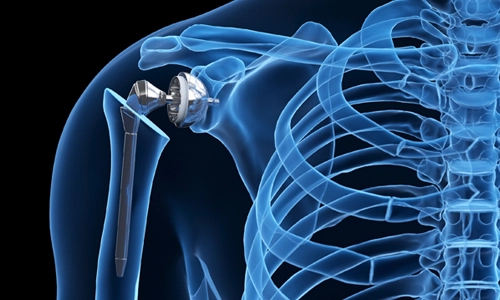

Artroskopik Cerrahi

Minimal invaziv artroskopik cerrahi teknikleri ile eklem problemlerinin tedavisi.